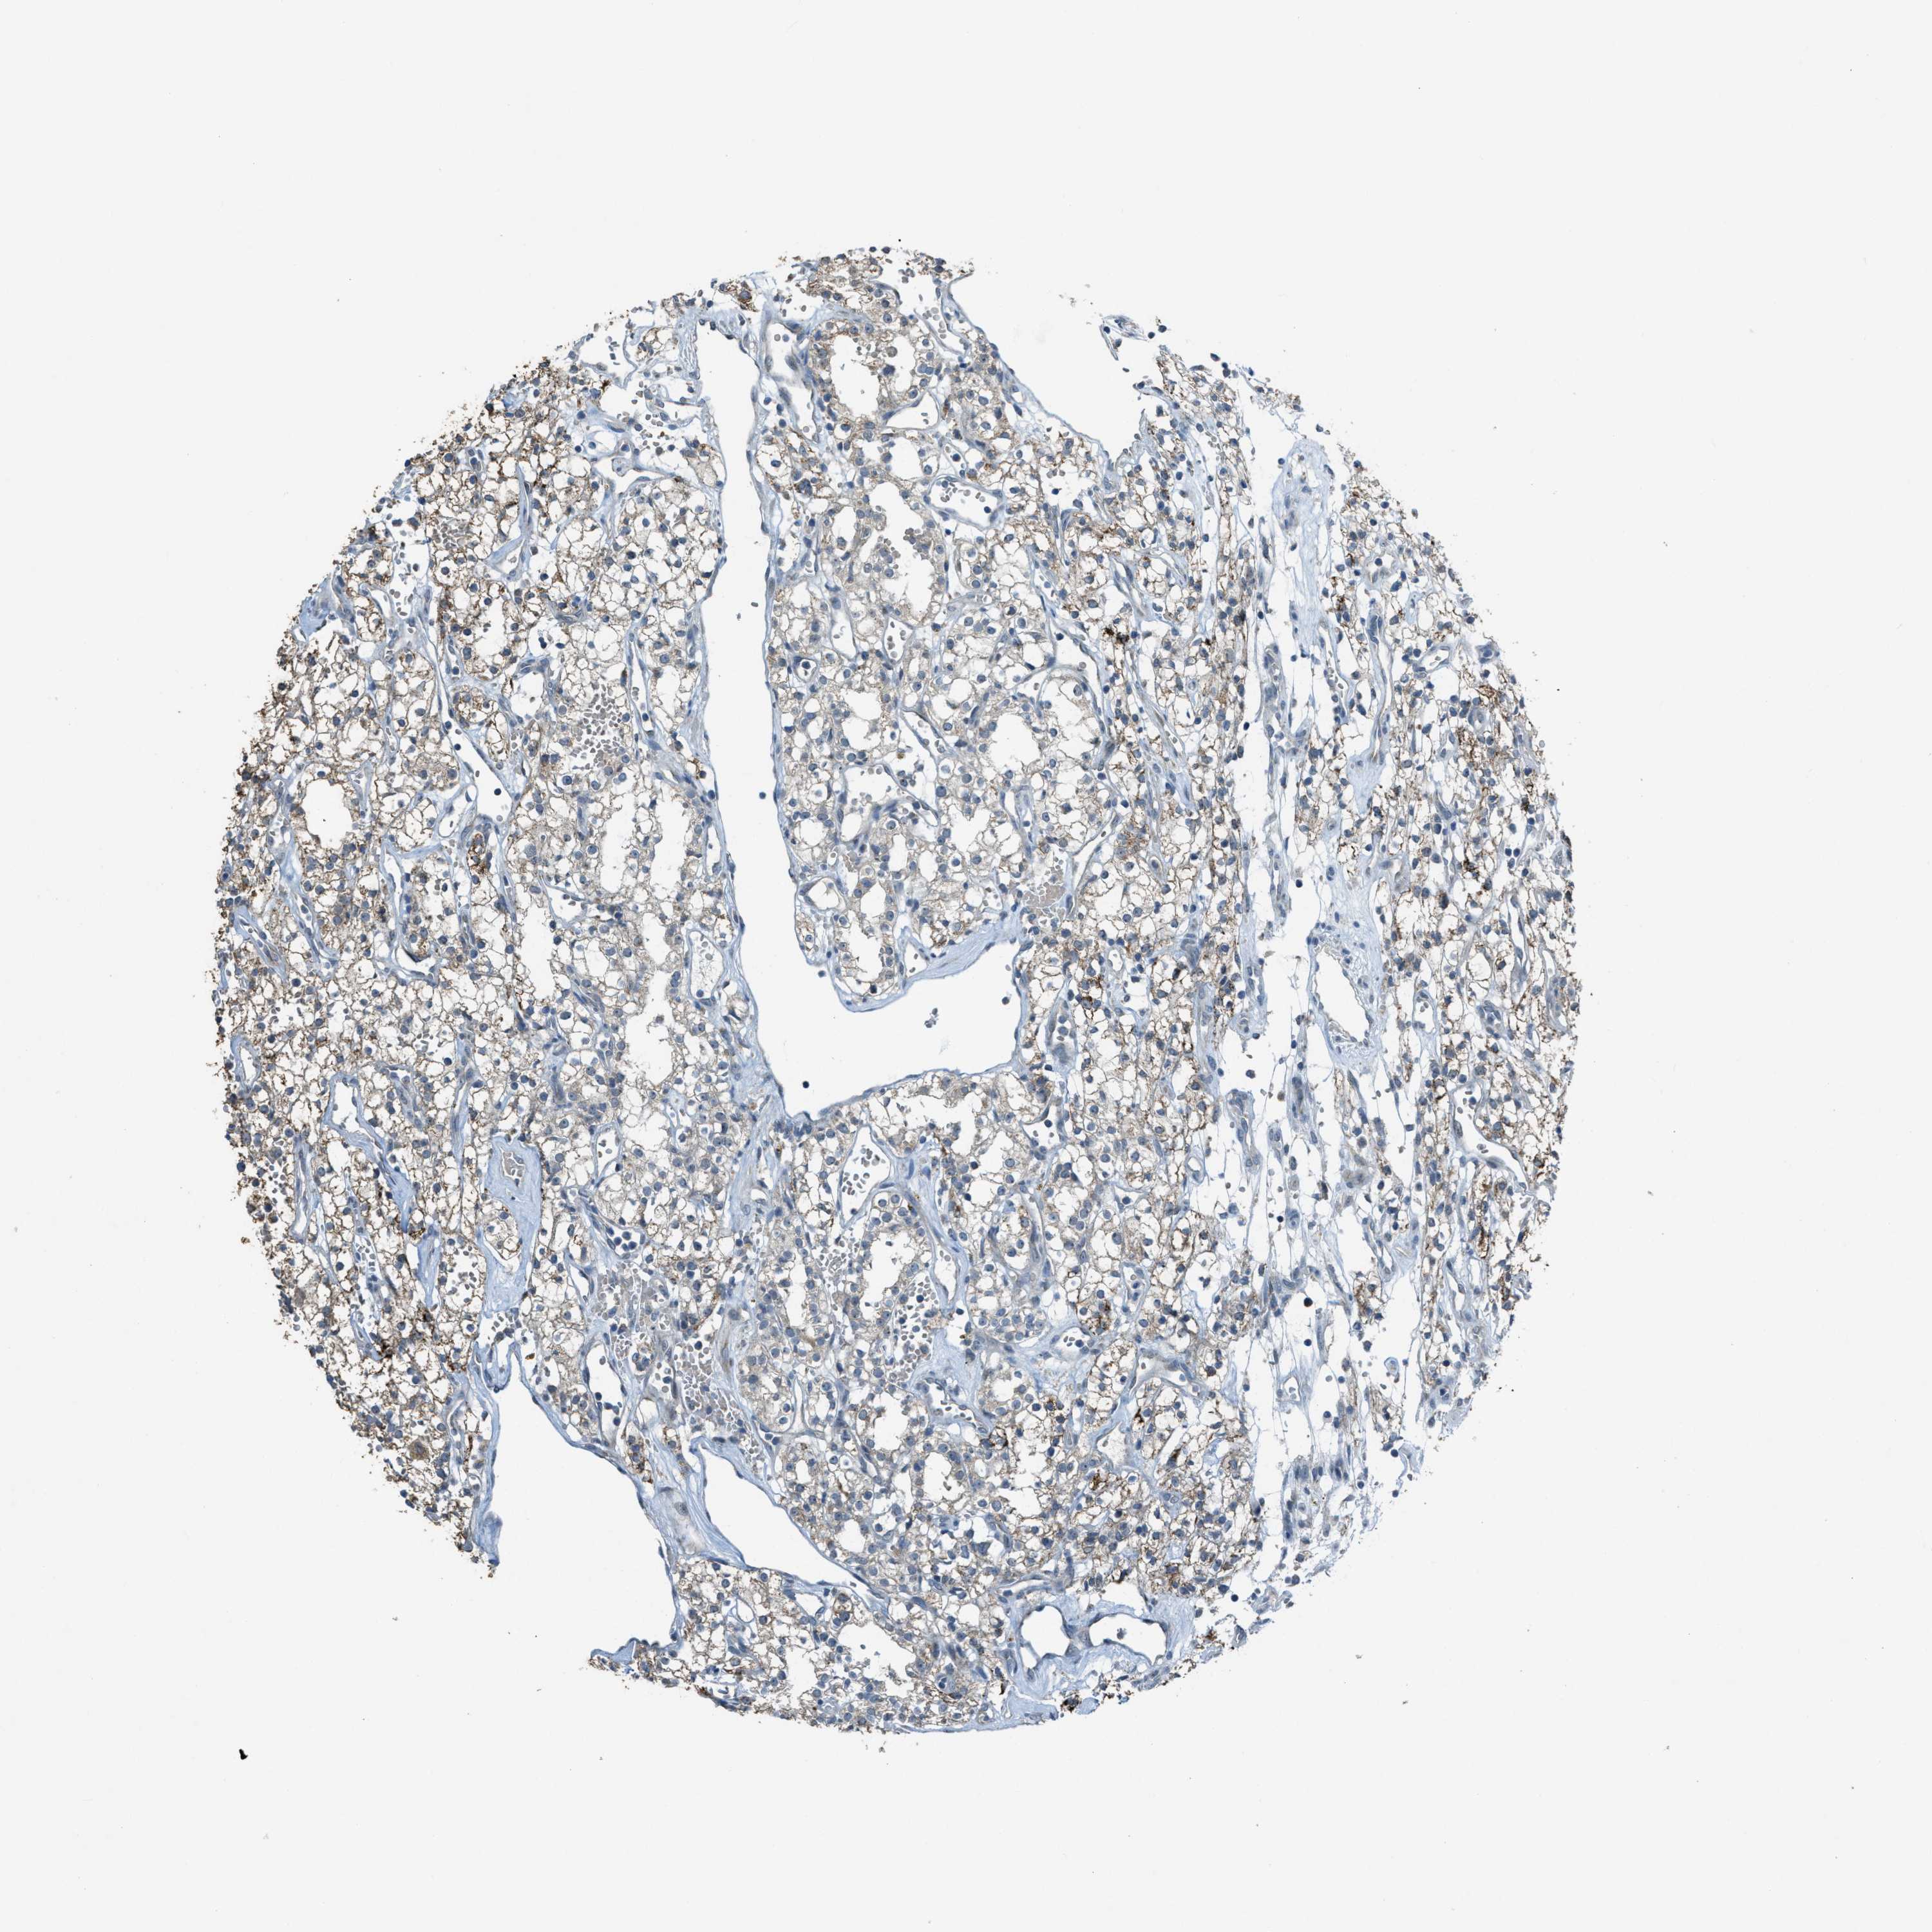

KIDNEY RENAL CLEAR CELL CARCINOMA (TCGA) - Interactive survival scatter ploti

The Survival Scatter plot shows the clinical status (i.e. dead or alive) for all individuals in the patient cohort, based on the same data that underlies the corresponding Kaplan-Meier plots. Patients that are alive at last time for follow-up are shown in blue and patients who have died during the study are shown in red.

The x-axis shows the expression levels (FPKM) of the investigated gene in the tumor tissue at the time of diagnosis. The y-axis shows the follow-up time after diagnosis (years). Both axes are complimented with kernel density curves demonstrating the data density over the axes. The top density plot shows the expression levels (FPKM) distribution among dead (red) and alive patients (blue). The right density plot shows the data density of the survived years of dead patients with high and low expression levels respectively, stratified using the cutoff indicated by the vertical dashed line through the Survival Scatter plot. This cutoff is automatically defined based on the FPKM cutoff that minimizes the p-score. The cutoff can be changed by dragging the vertical line or by entering a cutoff value in the square labeled "Current cut-off".

Under the Survival Scatter plot the p-score landscape (black curve; left axis) is shown together with dead median separation (red curve; right axis). Dead median separation is the difference in median mRNA expression between patients who have died with high and low expression, respectively. It is calculated as follows: median FPKM expression of dead patients with high expression - median FPKM expression of dead patients with low expression. This is intended to aid the user in visually exploring custom cutoffs and the associated p-scores and dead median separation.

Individual patient data is displayed and can be filtered by clicking on one or more of the category buttons on the top of the page. Categories describing expression level and patient information include: high, low, alive, dead, female, male and tumor stages. The scale of the x-axis can be toggled between linear and log-scale by clicking on the "x log" button. Mouse-over function shows TCGA ID, patient information and mRNA expression (FPKM) for each patient.

& Survival analysisi

Kaplan-Meier plots summarize results from analysis of correlation between mRNA expression level and patient survival. Patients were divided based on level of expression into one of the two groups "low" (under cut off) or "high" (over cut off). X-axis shows time for survival (years) and y-axis shows the probability of survival, where 1.0 corresponds to 100 percent.

CDON is not prognostic in Kidney Renal Clear Cell Carcinoma (TCGA)

Best expression cut offi

Based on the FPKM value of each gene, patients were classified into two groups and association between prognosis (survival) and gene expression (FPKM) was examined. The best expression cut-off refers the FPKM value that yields maximal difference with regard to survival between the two groups at the lowest log-rank P-value. Best expression cut-off was selected based on survival analysis .

: 1.85

Average pTPM 4.7

Number of samples 521